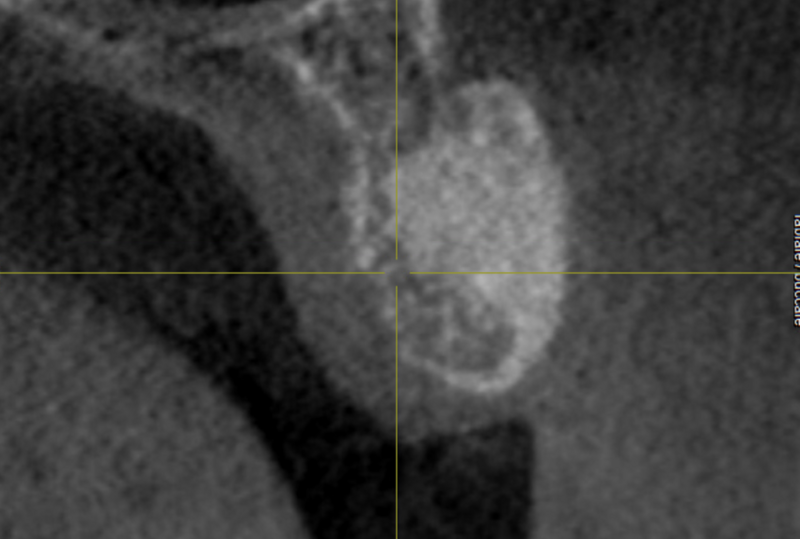

GREFFE OSSEUSE SOUS SINUSIENNE ET RECONSTRUCTION DE CRETE EN EPAISSEUR

AVANT APRES ELEVATION OSSEUSE SOUS-SINUSIENNE